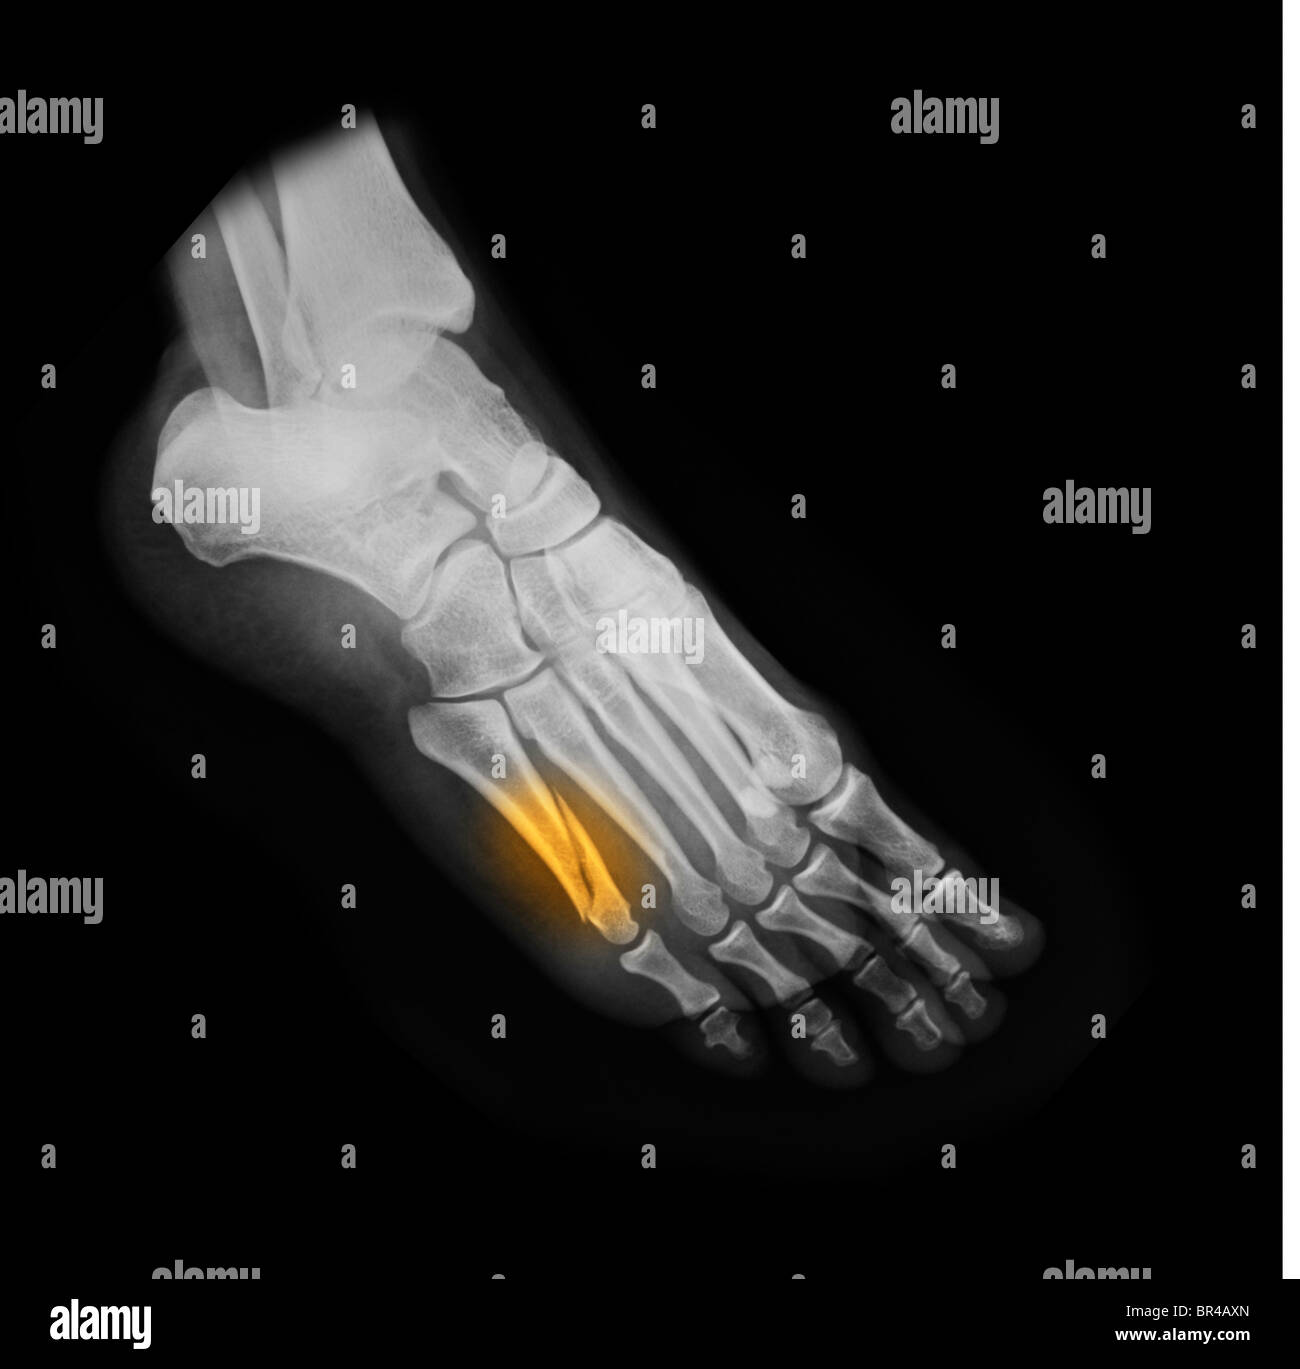

RMBR4J1F–X-ray pied d'une femme de 53 ans qui a frappé son pied et s'est fracturé la phalange proximale de son petit orteil